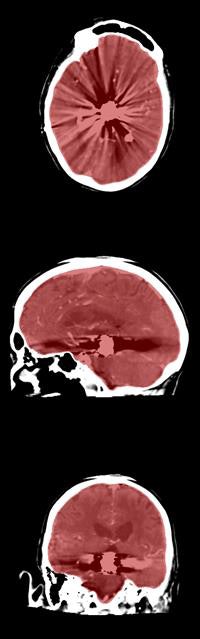

In their study, Dutch researchers developed a way to use software to automatically segment the cranial cavity based on anatomy borrowed from multiple image atlases, then refined the segmentation based on the patient's head CT data. The results closely correlated with manual segmentation of the cranial cavity in CT studies, validating the approach in a database of almost 600 patients.

The data in the atlas define the anatomy in the cranial cavity, thereby enabling an early approximation of the patient's cranial cavity via image registration, the authors explained. After initial segmentation, the details are refined using the sharp natural gradient between the intracranial tissue and the skull.

Labels for the registered atlas are then fused to create an initial approximation of the patient's cranial cavity, which is used to create a multistage geodesic active contour levelset method, where levelset represents an evolving surface steered by image information.

The gradient at the inner edge of the skull served as a boundary to stop propagation of the segmentation process. The first stage of refinement enables correction of errors that might be introduced during image registration while also allowing fast propagation of the initial segmentation. The second stage refines segmentation along the inner boundary of the skull.

The multiatlas registration results showed a high degree of overlap with the reference standard, yielding a mean Dice similarity coefficient of 0.973 ± 0.035, and adding levelset refinement increased the value to 0.984 ± 0.026.

The results encompass a large spectrum of anatomical and pathological variations seen in everyday clinical practice, and they closely approach the high performance of expert manual annotation, the authors wrote.